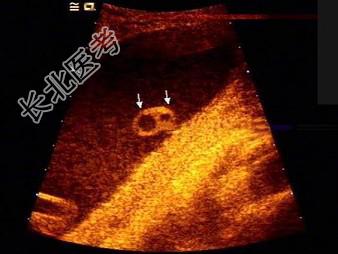

- 单项选择题如图,为一孕妇34周时, 羊水内漂浮所见管道结构(横切),最可能的诊断是   (   )

A、脊柱裂

B、淋巴管囊肿

C、脑膜膨出

D、正常图像

E、单脐动脉